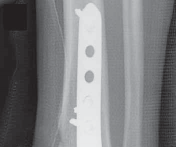

3.

Currently, “anatomically” contoured low-profile, small-fragment plates (with locking capability) designed for the distal tibia are available from most implant vendors.

1.

The anatomic design of these implants affords a satisfactory match to the anteromedial or anterolateral ( TECH FIG 5) surface of the distal tibia.

59.

Traditionally, we have used the small fragment plates, which allow easy and precise contouring for an appropriate bony fit.

60.

Nonlocking screws are used first to bring the plate in close apposition to bone to minimize the plate’s prominence against the soft tissues.

61.

Subsequent insertion of locking screws, creating a “hy-brid” internal fixation construct, is determined based on factors such as bone quality, comminution, and expected time to healing.

62.

An anterior plate location is often best for neutralization or buttressing of complex intra-articular fractures. TECH FIG 5 • A,B. Lag screws are used and anterior plating is performed to optimize fixation of the articular segment with a raft of anterior–posterior screws. Autograft from the tubercle of Gerdy was used above the disimpacted articular surface, but allograft or substi- A B tutes may be used.